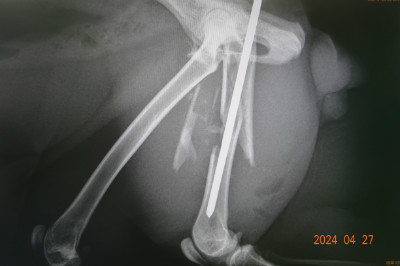

古い骨折の手術('24.4.27)

大腿骨を骨折したネコが来ました。

事故後、日数が経過していましたので、砕けた骨片等は筋肉とひっついて、困難な手術になりました。

翌日に退院して、1ヶ月後にピンを抜く頃には、回復していると思われます。